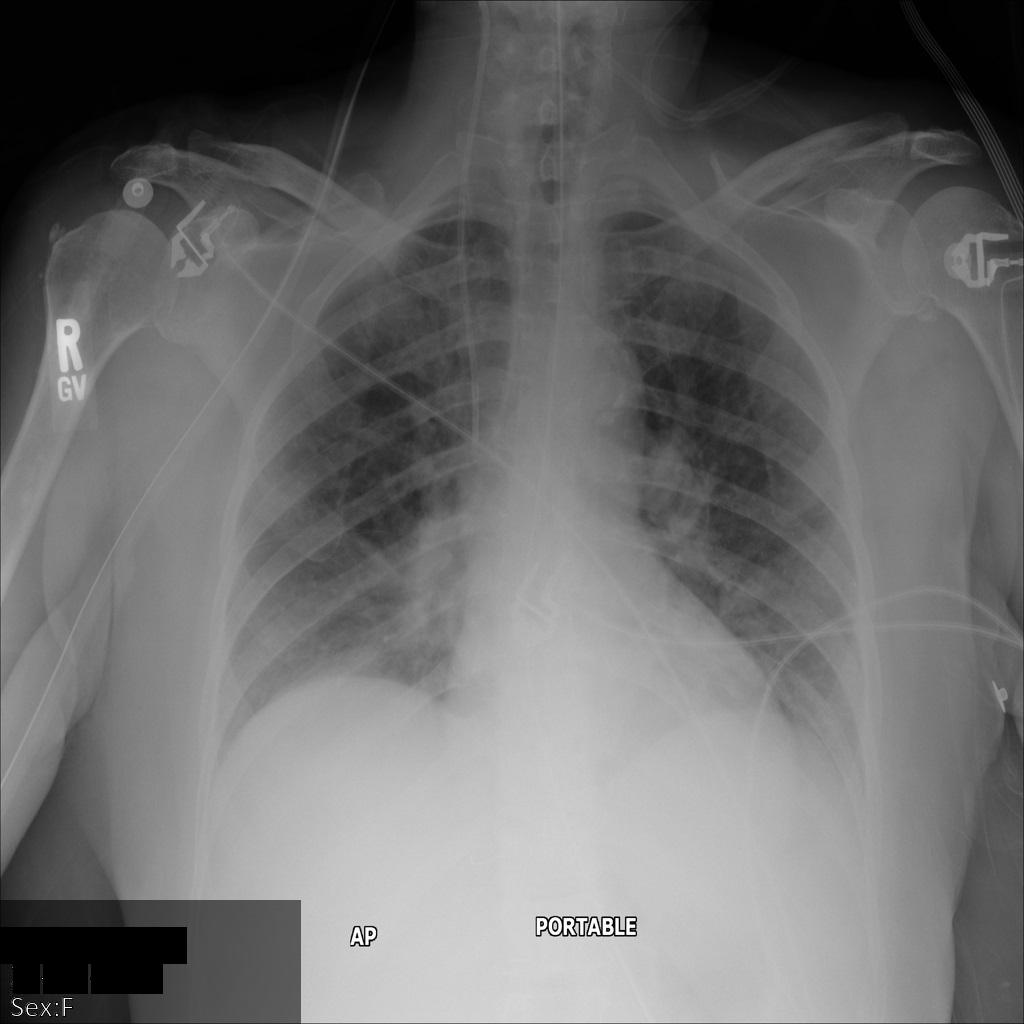

以下各部分提供的示例展示了如何使用各种方法对 DICOM 数据进行去标识化。每个示例都会提供去标识化后的图片输出。每个示例都使用以下原始图片作为其输入:

xray_original

您可以将每个去标识化操作的输出图片与该原始图片进行比较,以查看该操作的效果。